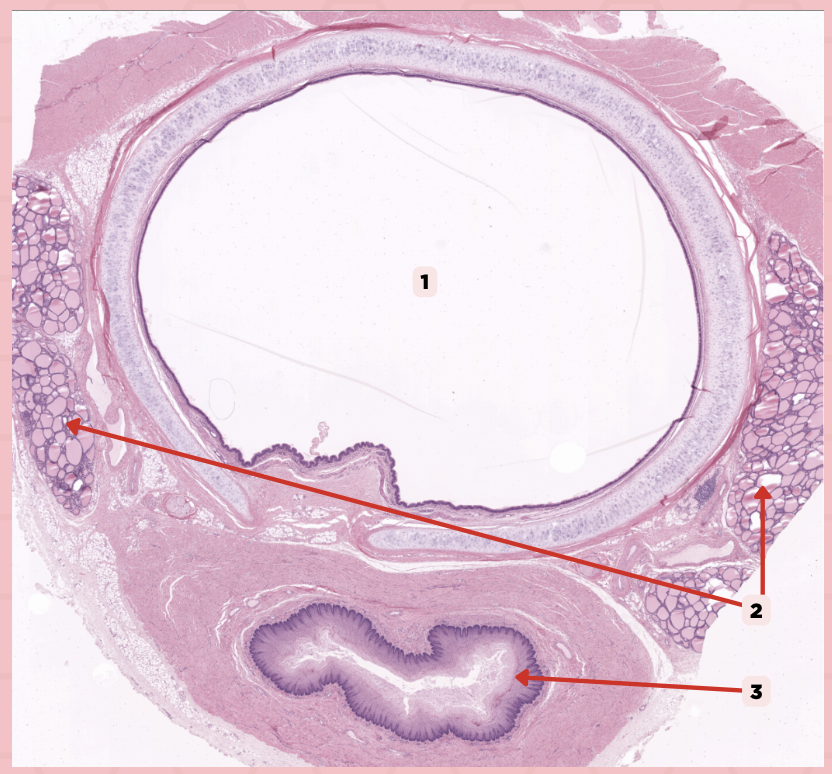

Lumen

It is a large ovoid space that occupies the center of the trachea.

Thyroid gland

This consist of cystic structures that contain highly eosinophilic material on either side of the trachea.

Lumen

Identify the structure labeled as 1.

Thyroid Gland

Identify the structure labeled as 2.

Esophagus

Identify the structure labeled as 3.

Ciliated Pseudostratified Columnar Epithelium

What is the epithelium of no. 3?

MALT

What type of lymphoid tissue supplies no. 3?